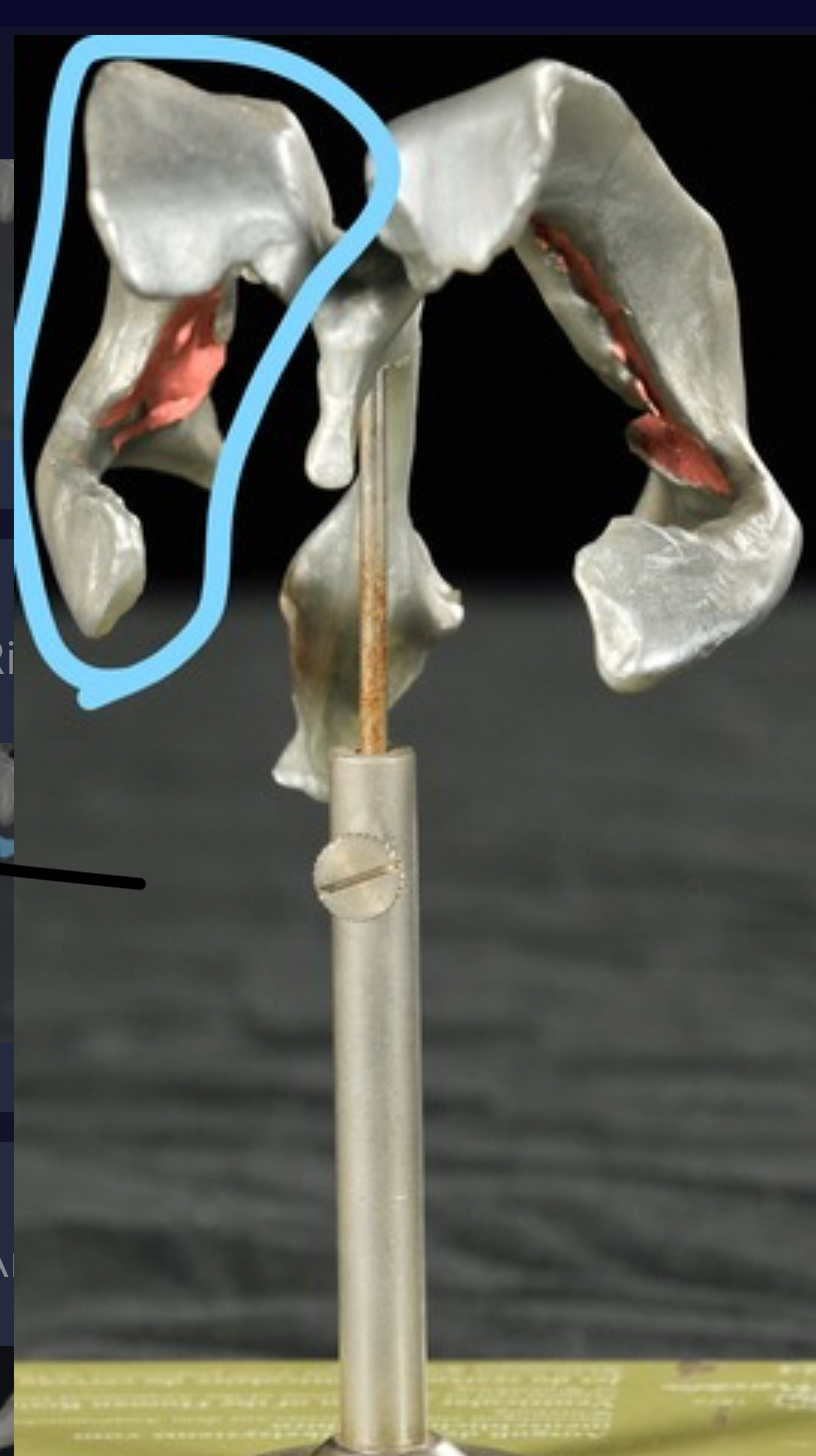

Left lateral ventricle

Right lateral ventricle

Anterior horn of ventricle

Posterior horn of ventricle

Inferior horn of ventricle

Third ventricle

Cerebral aqueduct

Fourth ventricle of stick model